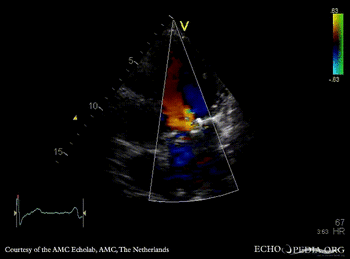

E00596.gif E00597.gif

PLAX: mechanical mitral valve prosthesis, dilated left ventricle and left atrium PLAX with Color Dopler: no mitral regurgitation